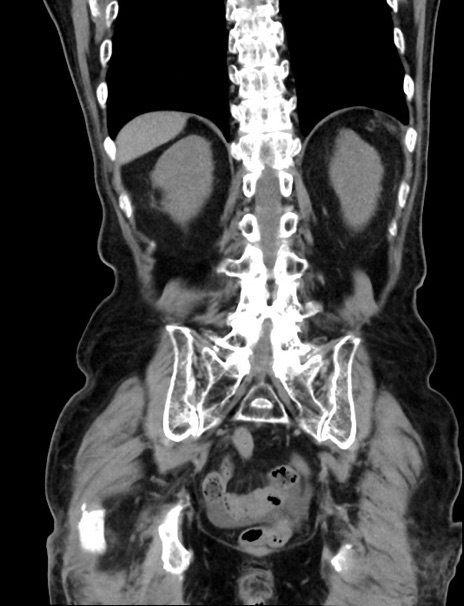

症例33(冠状断像)

【症例】70歳代 女性

【主訴】心窩部痛

【現病歴】延髄病変の精査・加療にて神経内科入院中。本日より心窩部痛あり。

【既往歴】虫垂炎

【身体所見】右下腹部を中心に圧痛と反跳痛あり。

【データ】WBC 10900、CRP 0.02